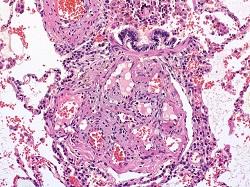

Hoping to change the uncertainty surrounding diagnosis and therapy, Everett and his colleagues developed a new test to measure levels of HDGF in blood, which, Everett says, is a growth factor protein important for the formation of new blood vessels in the lung -- a process known to readily occur in the lungs of patients with pulmonary hypertension. His research group compared blood samples from 39 patients with severe pulmonary arterial hypertension who had failed treatment for pulmonary arterial hypertension and were waiting for lung transplants, and a control group of 39 age, gender and race-matched healthy volunteers. They found median protein levels were about seven times higher than in controls, with a median of 1.93 nanograms per milliliter in patients and a median of 0.29 nanograms per milliliter in the controls.

Although the biochemical details of why there is a link between pulmonary arterial hypertension and HDGF remain unknown, Everett suspects levels of the growth factor might increase to spur blood vessel healing when arteries stretch in the lungs due to pulmonary arterial hypertension. HDGF is unique to current clinical measures of pulmonary hypertension, as it does not come from the heart and reflects more specifically how the disease affects the lungs, he says.